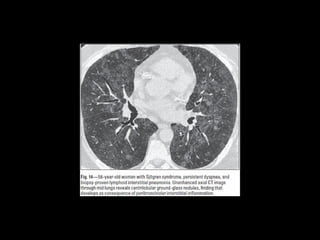

DD UIP CT •AR, Esclerodermia (esófago dilatado) • Asbestosis ( derrame pleural, bandas parenquimatosas) • Neumonitis por hipersensibilidad crónica: fijarse en signos de atrapamiento aéreo, Respeto de bases o cuando hay nódulos centrolobulillares. • Sarcoidosis terminal: fibrosis en segmentos posteriores de lóbulos superiores o perihiliar, o nódulos perilinfáticos. • NSIP • Complicaciones: • Exacerbación, DAD • Cáncer pulmonar 10-15% bases

• 22.

NSIP • + asociadoa otras condiciones esclerodermia, poliomiositis, dermatomiositis, toxicidad a drogas, inmunodeficiencia. • Mejor pronóstico • 40-50 h=m

• 23.

NSIP Histología • Continuode componente celular a fibrosis • Plasmocitos y linfocitos • Engrosamiento intersticial por acumulación de colágeno • Homogeneidad • Biopsia es incompatible con otros patrones

• 24.

NSIP TC • Vidrioesmerilado bilat y simétrico, LS Reticulación fina, BQ por tracción, disminuciónd e volumen pulmonar, panalización leve Consolidaciones Exacerbaciones menos comunes que FPI • Pronóstico depende del grado de fibrosis • Celular: 100% sv Fibrótico: 5 años SV